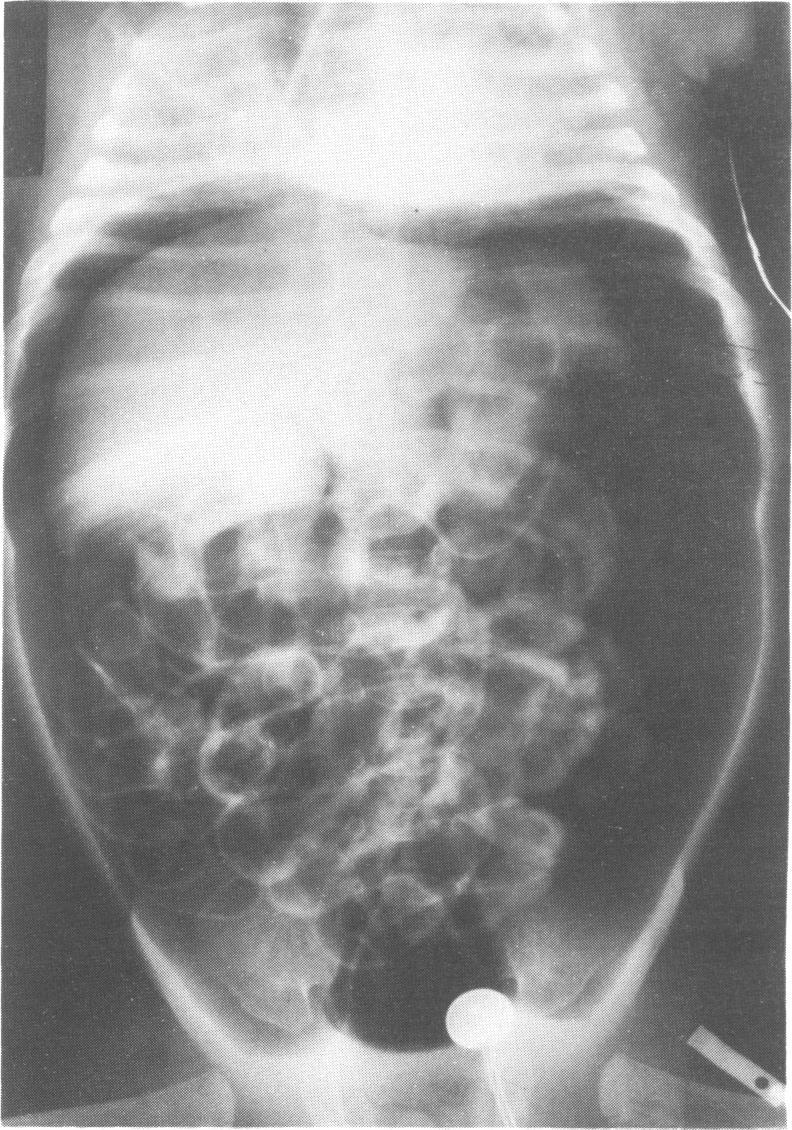

Three cases of gastroduodenal perforation and one case of ulceration and extreme thinning of the gastric wall occurred in preterm babies treated with dexamethasone for bronchopulmonary dysplasia. This complication of treatment with steroids has not to our knowledge previously been described in preterm infants. Urgent abdominal paracentesis was an essential part of the resuscitation in these cases, and this potentially serious side effect should be considered in all babies treated with steroids.